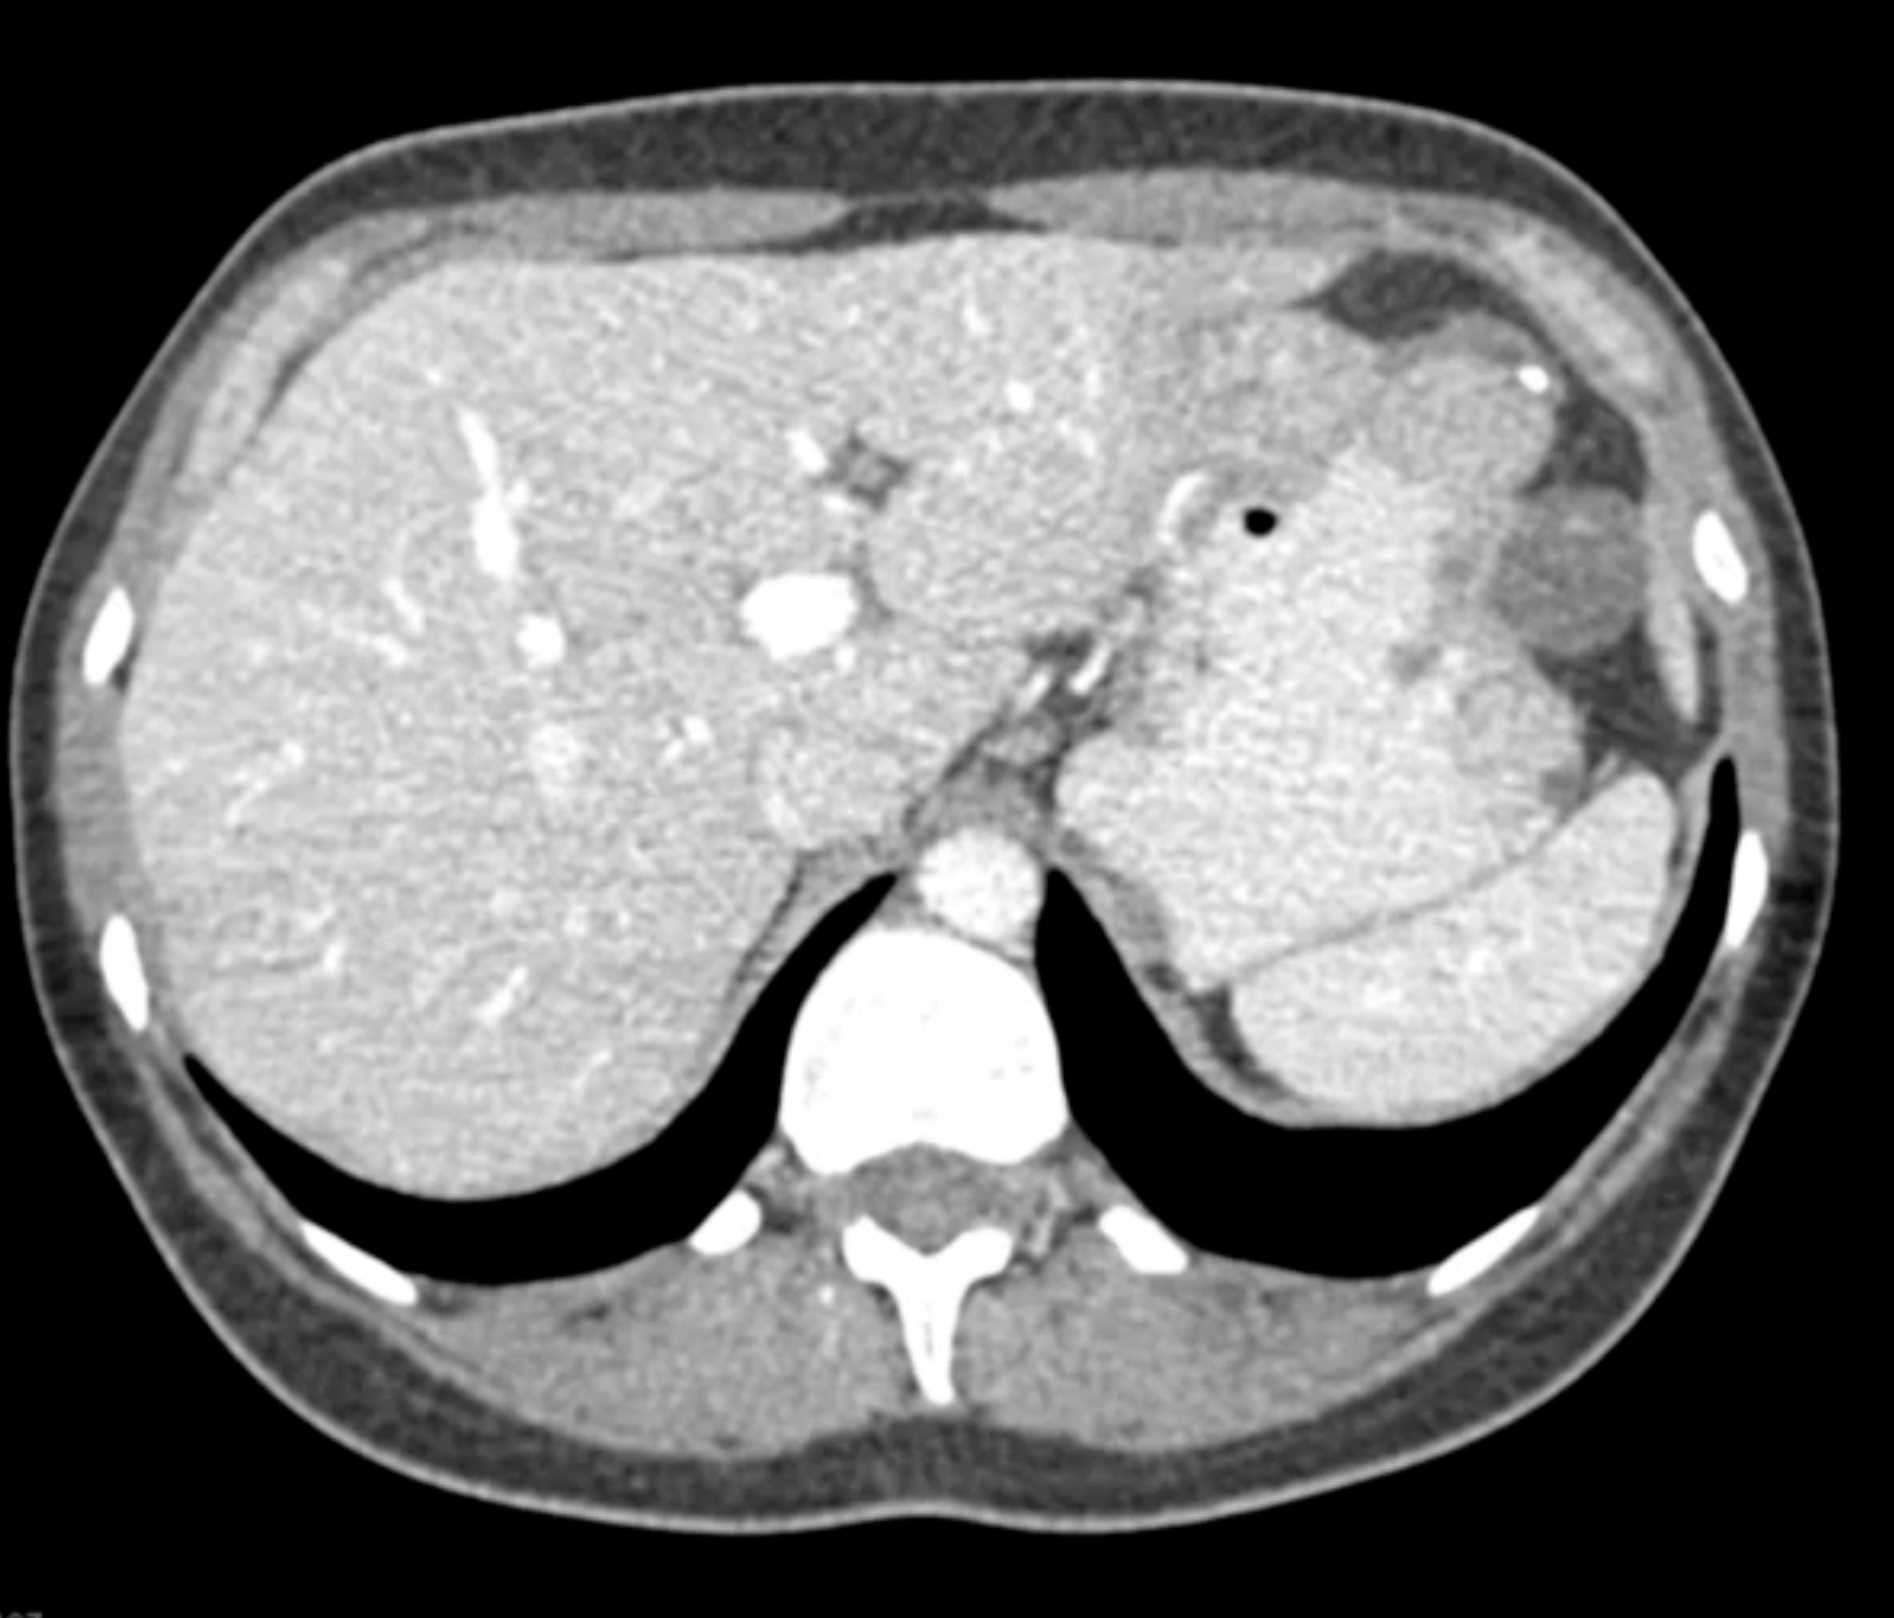

Multiple Gastric GIST Tumors with Spread to Nodes (Carney-Stratakis Syndrome)